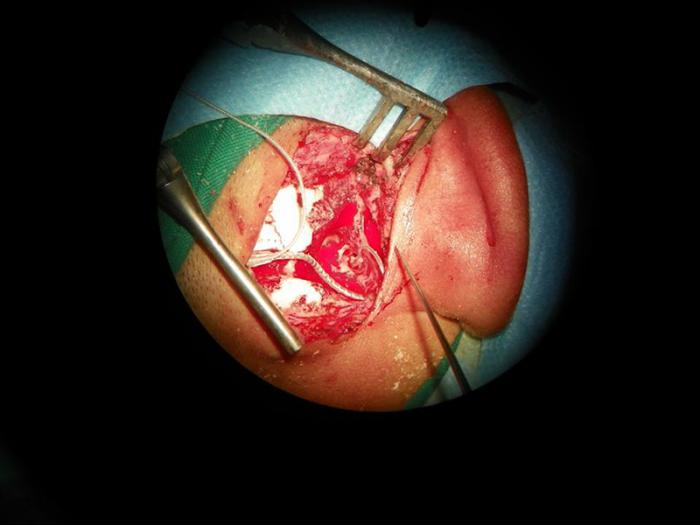

Para colocar un implante coclear se ejecuta una cirugía, pasando a través del hueso temporal del cráneo, que permita un acceso directo al oído interno. Una vez allí, se coloca un dispositivo que lanza una estimulación eléctrica, directa al mismo.

Una vez colocado el mecanismo, y antes de que pase el efecto de la anestesia, se le realiza al paciente una evaluación imagenológica, que certifica si el implante está situado correctamente. También se le practica la telemetría, una prueba mediante la cual se enciende el implante, y se evalúa su funcionamiento mediante un software. Entonces se sutura, se despierta al paciente, y se le mantiene en observación al menos 72 horas. A partir de ahí, se le da un seguimiento periódico y se espera entre tres y cuatro semanas para encender el dispositivo. A este último paso, se le conoce como Despertar.